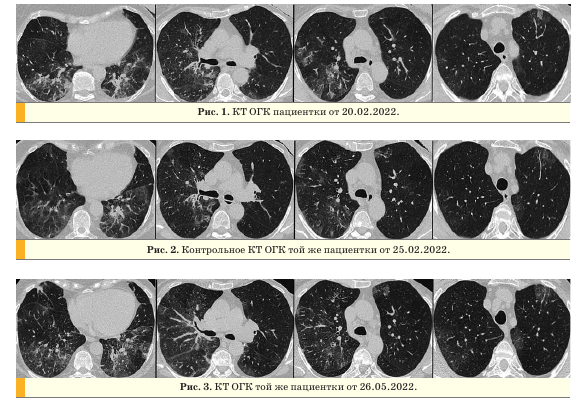

На компьютерных томограммах (КТ) органов грудной клетки (ОГК) от 20.02.2022 в обоих легких визуализировались участки по типу “матового стекла”, ретикулярные изменения, зоны консолидации, с поражением 45-50% в правом легком, 35% - в левом легком (рис. 1).

При контрольном обследовании через 4 дня отмечалась положительная динамика в виде уменьшения площади поражения и организации в линейные структуры, в правом легком - до 30%, в левом легком - до 20% (рис. 2).

После выписки из инфекционного стационара у пациентки сохранялся непродуктивный кашель. Амбулаторно выполнена КТ ОГК (26.05.2022), на которой на фоне ретикулярных изменений определялись двусторонние, преимущественно периферические, полисегментарные уплотнения по типу “матового стекла” с зонами консолидации, дисковидными ателектазами, в правом легком - единичные солидные узелки до 4,5 мм (рис. 3).